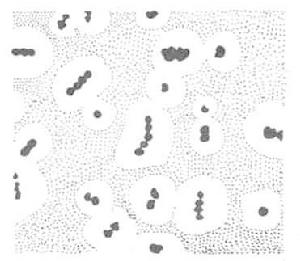

急性間質性腎炎的形態學特點是:間質單核細胞浸潤(尤其是皮質部),嗜酸性粒細胞(尤其在藥物引起者中)和少量嗜中性粒細胞也可以存在;炎症細胞可侵入小管壁,重症者可有區域性腎小管壞死;炎症可呈斑片狀或瀰漫性,其範圍常與腎功能損害程度相關;間質常有水腫,急性期並無纖維化;除少數可有系膜增多外,腎小球常完好。目前研究證實,腎內浸潤的單核細胞是T淋巴細胞,包括輔助/誘導細胞和抑制/細胞毒細胞都存在。這些觀察提示T細胞介導的遲發超敏反應和細胞毒T淋巴細胞損傷作用都參與了本病的發病機理。在免疫螢光檢查中可見部分病例間質和腎小管基底膜上有免疫球蛋白和補體沉積,在電鏡下則為電子緻密物,提示系免疫複合物。少數病人可見小管基底膜上有IgG和C3線狀沉積,提示抗腎小管基底膜抗體也參與了本病的發病機理。臨床表現